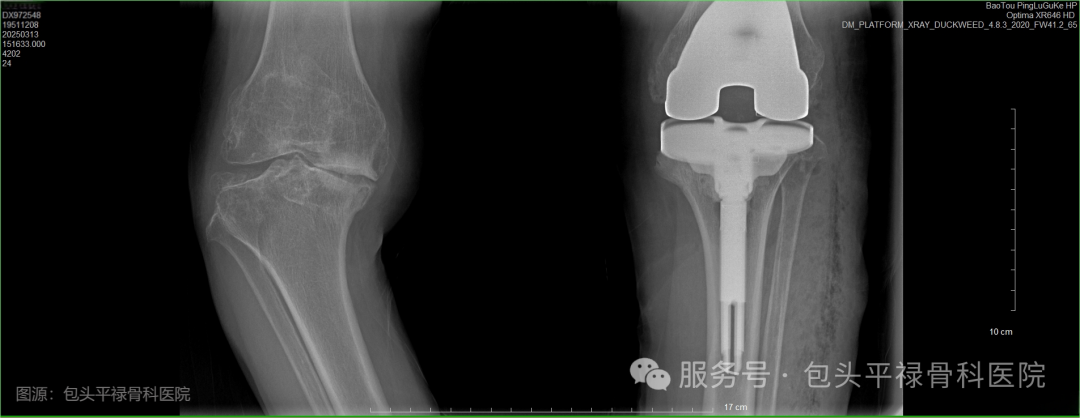

人工膝关节置换术前VS术后

老年患者左膝术前VS康复治疗仪VS患者术后复查